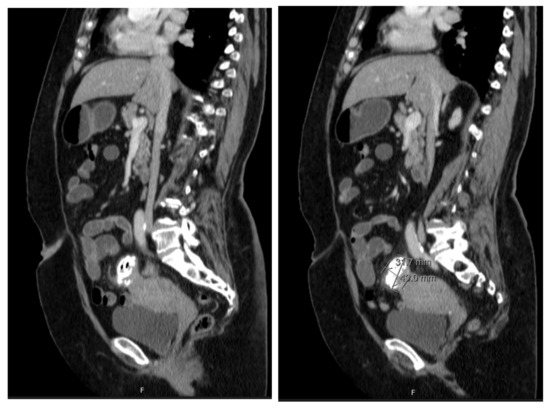

The patient underwent a Computed Tomography (CT) Enterography requested by the gastroenterologist. This exam showed a mass adjacent to the uterine fundus and in continuity with the sigmoid colon wall, with a nodular and exophytic appearance, dimensions of 3.4 × 3.2 × 4.3 cm, and identifiable calcifications and gas areas and conditioning a slight colonic retraction and fat enhancement in the surrounding area (Figure 2). The blood examinations and serum tumour markers (CA 125, CEA, and CA 19.9) were unremarkable.

Figure 2. CT enterography showing a nodular, exophytic, and extensively calcified formation with two gaseous points, with dimensions of 3.4 × 3.2 × 4.3 cm, in close proximity with uterine fundus and adjacent sigmoid colon and conditioning a slight colonic retraction and surrounding fat enhancement.

In our case, diagnoses using imaging or endoscopy were not completely conclusive. The CT enterography findings were suggestive of diverticulitis and colouterine fistula since it showed air bubbles adjacent to the uterine cavity and the colon wall joined to the uterus. Nevertheless, definitive diagnosis was limited because CT findings cannot accurately distinguish inflammatory from neoplastic disease and may not be conclusive when distinguishing a fistula tract from complicated diverticulitis.